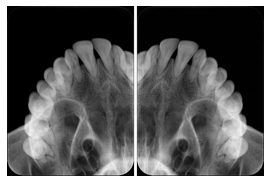

- OO-1. Intra-oral Full Mouth Series Structured Display